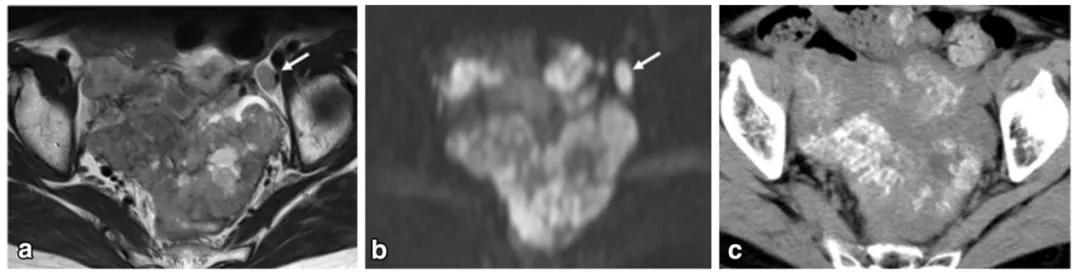

女,22 岁,无性细胞瘤。乳酸脱氢酶及碱性磷酸酶升高。T2WI 示右侧卵巢分叶状肿物(图 a),DWI 呈高信号(图 b),增强扫描明显强化(图 c)。箭头显示肿物内可见纤维血管分隔。

女,18 岁,卵黄囊瘤(右侧),AFP 升高。T2WI 示卵巢实性为主肿物(图 a),内见低信号纤维血管分隔(白箭),实性成分 DWI 呈高信号(图 b),增强扫描明显强化(图 c),内见无强化坏死区(箭头)。

女,12 岁,卵巢 Burkitt 淋巴瘤。双侧卵巢肿物,T2WI 信号稍高(图 a),DWI 呈高信号(图 b),增强扫描明显强化(图 c),箭头显示肿物边缘多发囊性结节,为卵泡保留征。

女,34 岁,胃癌双侧卵巢转移瘤。T2WI 显示双侧卵巢实性肿瘤,T2WI 呈高低混杂信号(图 a),DWI 呈高信号(图 b)。